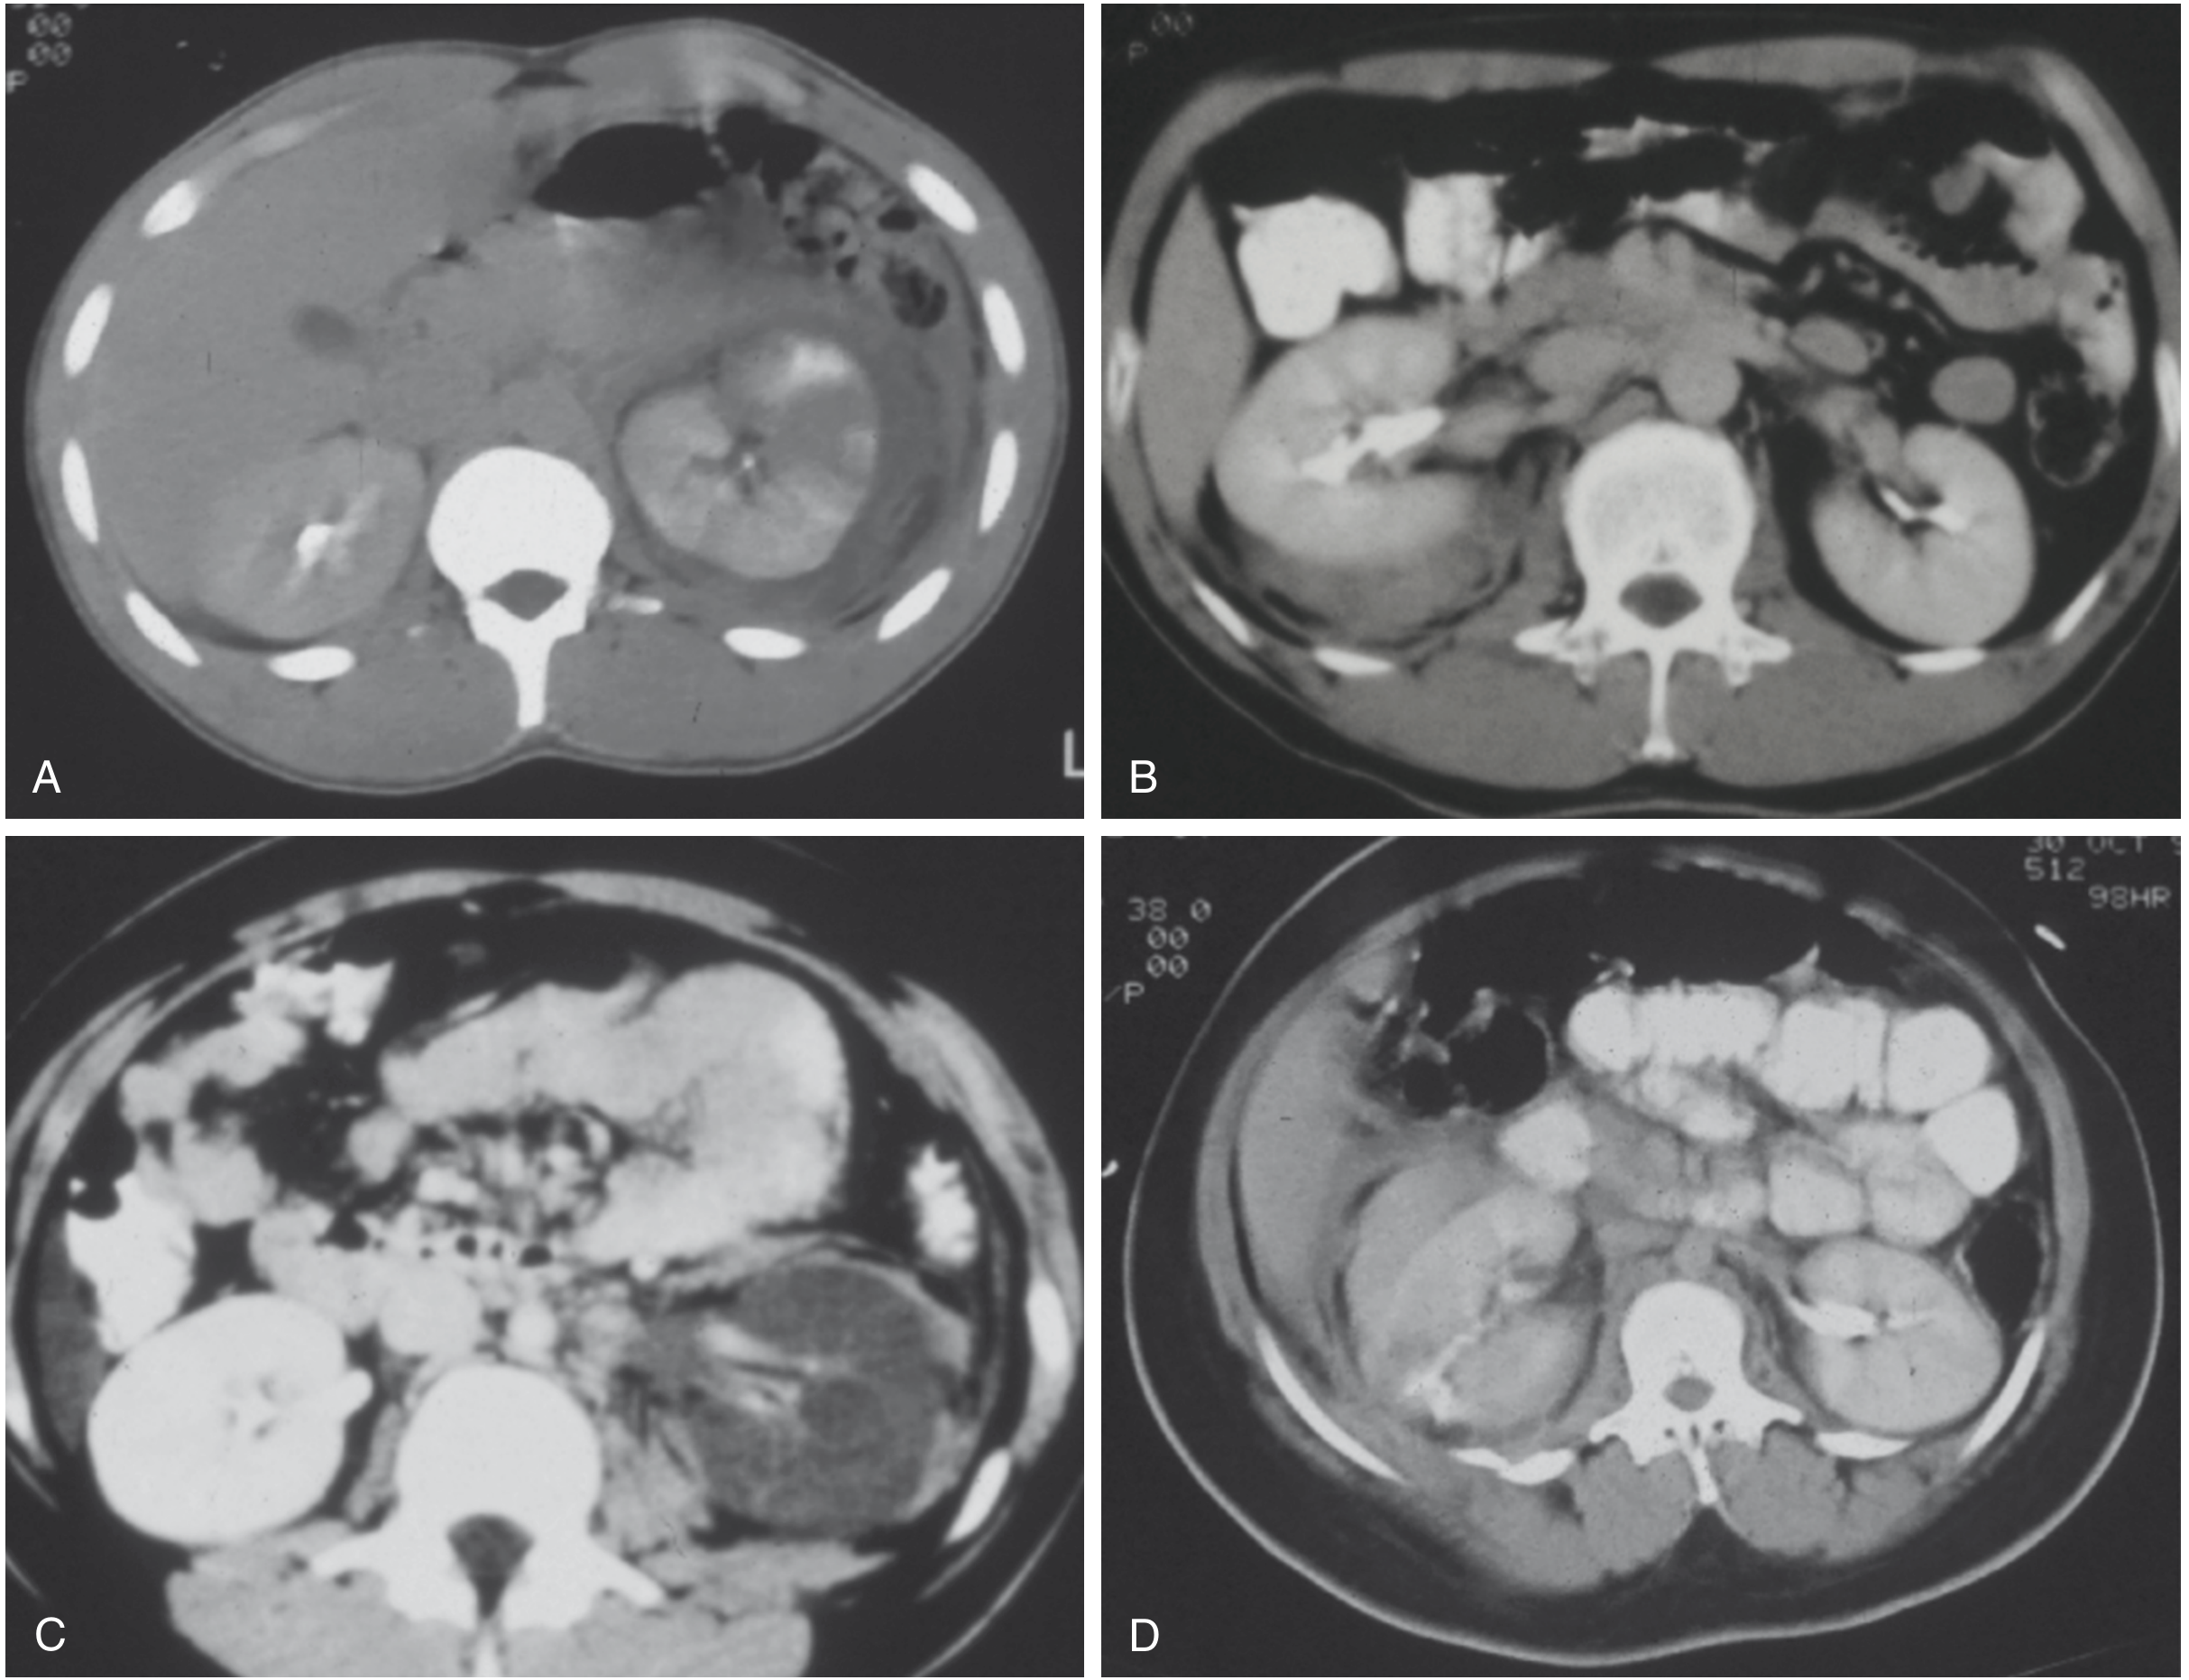

CT scans of renal trauma — Grades I, II, IV (x2)

CT scans showing renal trauma grades: (A) Grade I — left renal contusion with heterogeneous enhancement; (B) Grade II — small right posterior perirenal haematoma; (C) Grade IV — left renal artery thrombosis without active bleeding; (D) Grade IV laceration with posterolateral contrast extravasation. — Sabiston Textbook of Surgery, Fig. 39.1

CT Appearance by Grade

• Grade I: Ill-defined low-attenuation areas within parenchyma (contusion); non-enlarging subcapsular haematoma crescentic in shape

• Grade II: Cortical laceration <1 cm; small perirenal haematoma contained in Gerota fascia

• Grade III: Laceration >1 cm into medulla, larger perirenal haematoma still within Gerota fascia

• Grade IV: Laceration extending into collecting system with urinary extravasation; segmental renal infarction

• Grade V: Shattered kidney; avulsion of hilar vessels; devascularized kidney

Grainger & Allison's Diagnostic Radiology, Table 36.2, p. 921